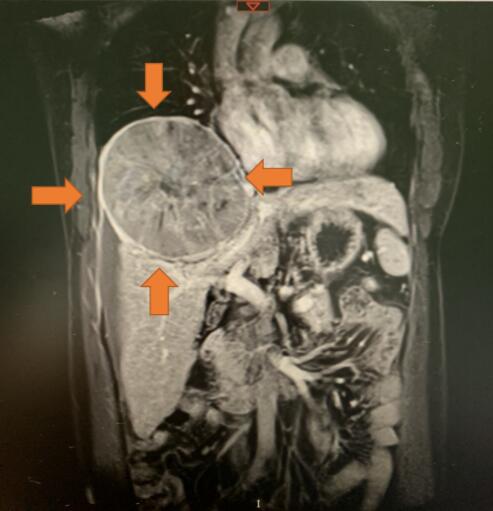

在4月底的一個深夜,韋先生突然被腹部的一陣劇痛驚醒,一家人急忙來到醫院就診,初步檢查發現肚子裏面竟然從肝臟長出一個巨大的腫瘤,經過第二天的CT檢查進一步確認了病情,腫瘤直徑大約15cm,就像一個小皮球那麼大,同時腫瘤向上生長擠壓右側的肺部,更糟糕的是由於腫瘤太大已經有破裂出血,如果再不及時治療可能就會有生命危險。

經過一系列檢查,患者各項指標滿足手術條件,而且腫瘤沒有轉移到其他部位。吳凡介紹說,患者的腫瘤長在肝臟的中心部位,屬於手術難度較高的中央型肝癌,這種手術既要完整切除腫瘤又不能損傷通往肝臟左側及右側的管道系統。因為一旦損傷,患者的肝臟將遭到不可逆轉的影響,甚至因為肝功能衰竭導致死亡。

吳凡醫生與遠在北京總院肝膽外科的吳健雄教授進行了遠程會診,吳健雄針對患者的情況給予了深圳團隊細緻的指導,也給整個治療小組很大信心。另外巨大的肝癌侵犯了右側胸腔大片的膈肌,必須要有胸外科專家配合手術,車旭邀請了赫捷院士的博士後、胸外科病區主任郭曉彤教授會診,郭曉彤教授在手術台上反覆推敲手術切口的位置及影響,給手術成功奠定了堅實的基礎。